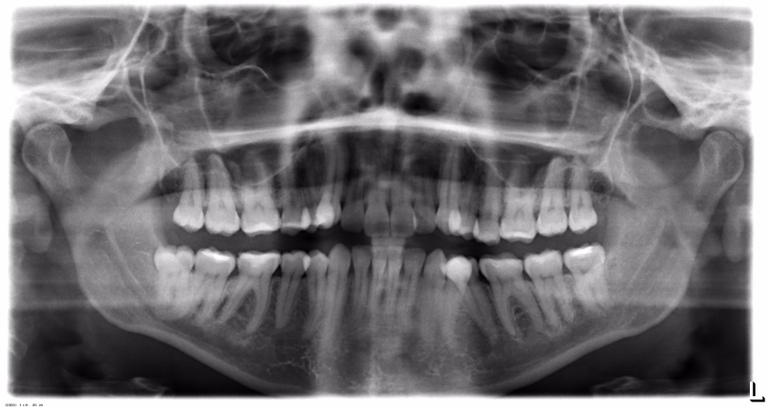

UPD: рентген (прицельный может переделать? на всякий случай панорамный)

Помогите, пожалуйста, определиться с дальнейшей тактикой лечения. Нижняя левая шестерка. Два месяца назад откололся небольшой кусок, поменяли старую пломбу. Потом периодически возникала несильная ноющая боль после твердой пищи, но проходила в течение суток. Оказалась завышена пломба, врач лишнее сточила, промыла карман. После этого появилась практически постоянная ноющая боль (не зависимо от чего-то), чувствительность на холодное, практически не жую на этой стороне. Врач сделала снимок, по ее словам пульпа достаточно далеко от пломбы, зуб в порядке, но глубокий карман. Карман лечили в течении двух недель (йодоформными турундами). По словам врача теперь кармана нет. Но боль продолжается. Собственно, что делать дальше???